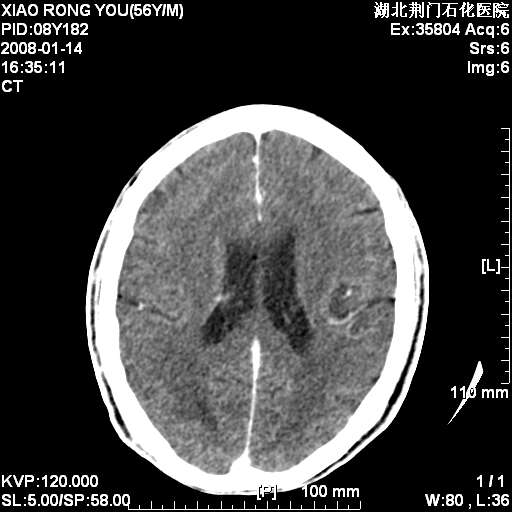

男性,68岁,多年肺结核病史。最近ct复查右肺有占位。

头部平扫